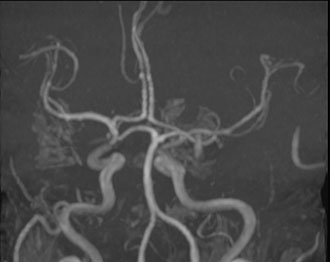

Mit der MRT-Angiographie können im Kernspin Zentrum Köln die Blutgefäße des Gehirns und der Halsregion ohne Kontrastmittelrisiko dargestellt werden. So lassen sich Aneurysmen, Angiome oder ein Gefäßverschluss zuverlässig erkennen. Diese Untersuchung ist insbesondere bei Durchblutungsstörungen, Schlaganfallverdacht oder Kopfschmerzen mit Gefäßbezug von großer Bedeutung.